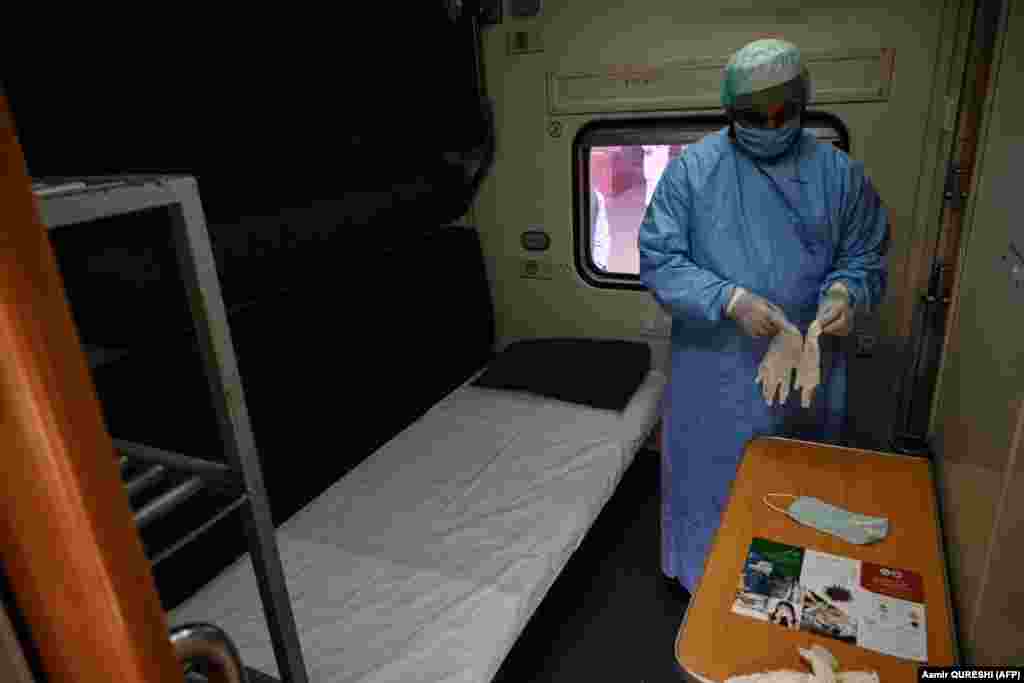

Опыт Китая, Италии, Испании, Франции и США показал, что медицинские учреждения могут «захлебнуться» от тысяч пациентов, нуждающихся в неотложной медицинской помощи. О тех мерах, на которые пришлось пойти правительствам разных стран в ожидании потока больных, рассказываем в фоторепортаже.

Опыт Китая, Италии, Испании, Франции и США показал, что медицинские учреждения могут «захлебнуться» от тысяч пациентов, нуждающихся в неотложной медицинской помощи. О тех мерах, на которые пришлось пойти правительствам разных стран в ожидании потока больных, рассказываем в фоторепортаже.